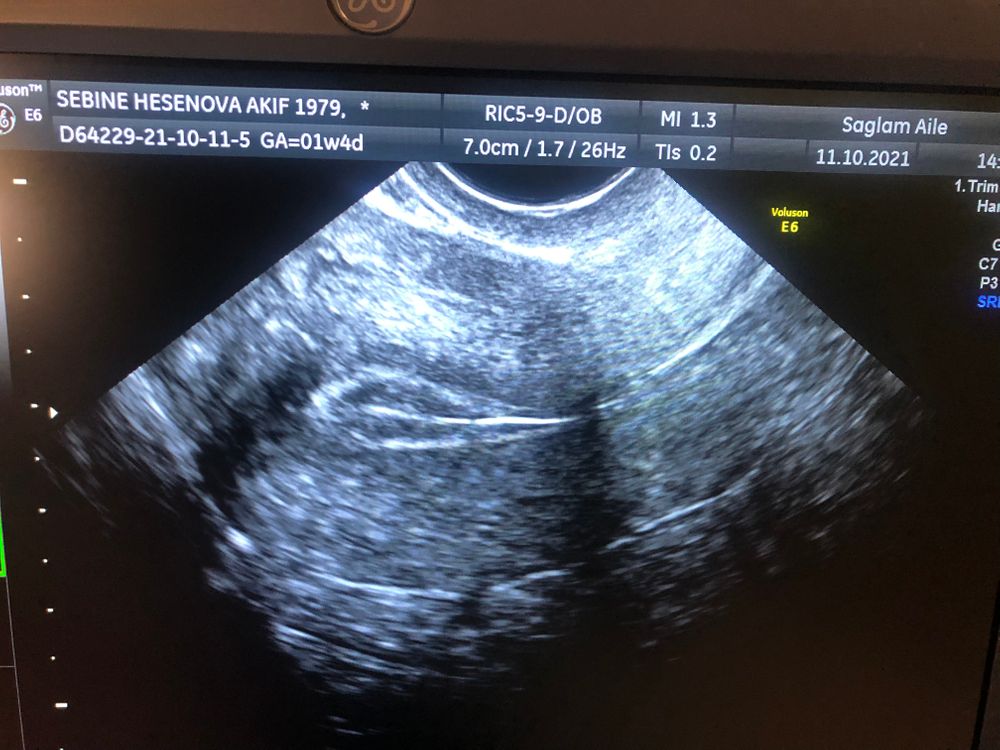

ФолликулометрияНа 12дц эндометрий был 7.3 ДФ 20мм, сеглня на 13 дц эндметрий сдулся 4.6 ДФ 21.6мм. Овуляции еще не было. Может быть что я попала в моменте овуляции и эндометрий сьежился и тд? Завтра тоже иду на узи, но судя по всему эндометрий уже не вырастет... Вдруг кто сталкивался с таким процессом. Фото прикрепляю.

12 ДЦ 7.3 мм